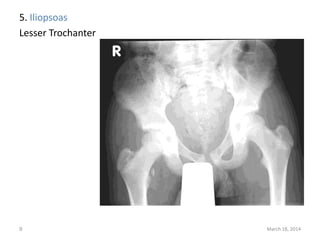

The document lists 10 common sites of avulsion fractures caused by the tearing away of tendons or ligaments from bone. It identifies the specific muscles or tendons that can cause avulsion fractures at the iliac crest, ischial tuberosity, greater trochanter, lesser trochanter, posterior calcaneus, olecranon process, superior patella, inferior patella, and tibial tuberosity.